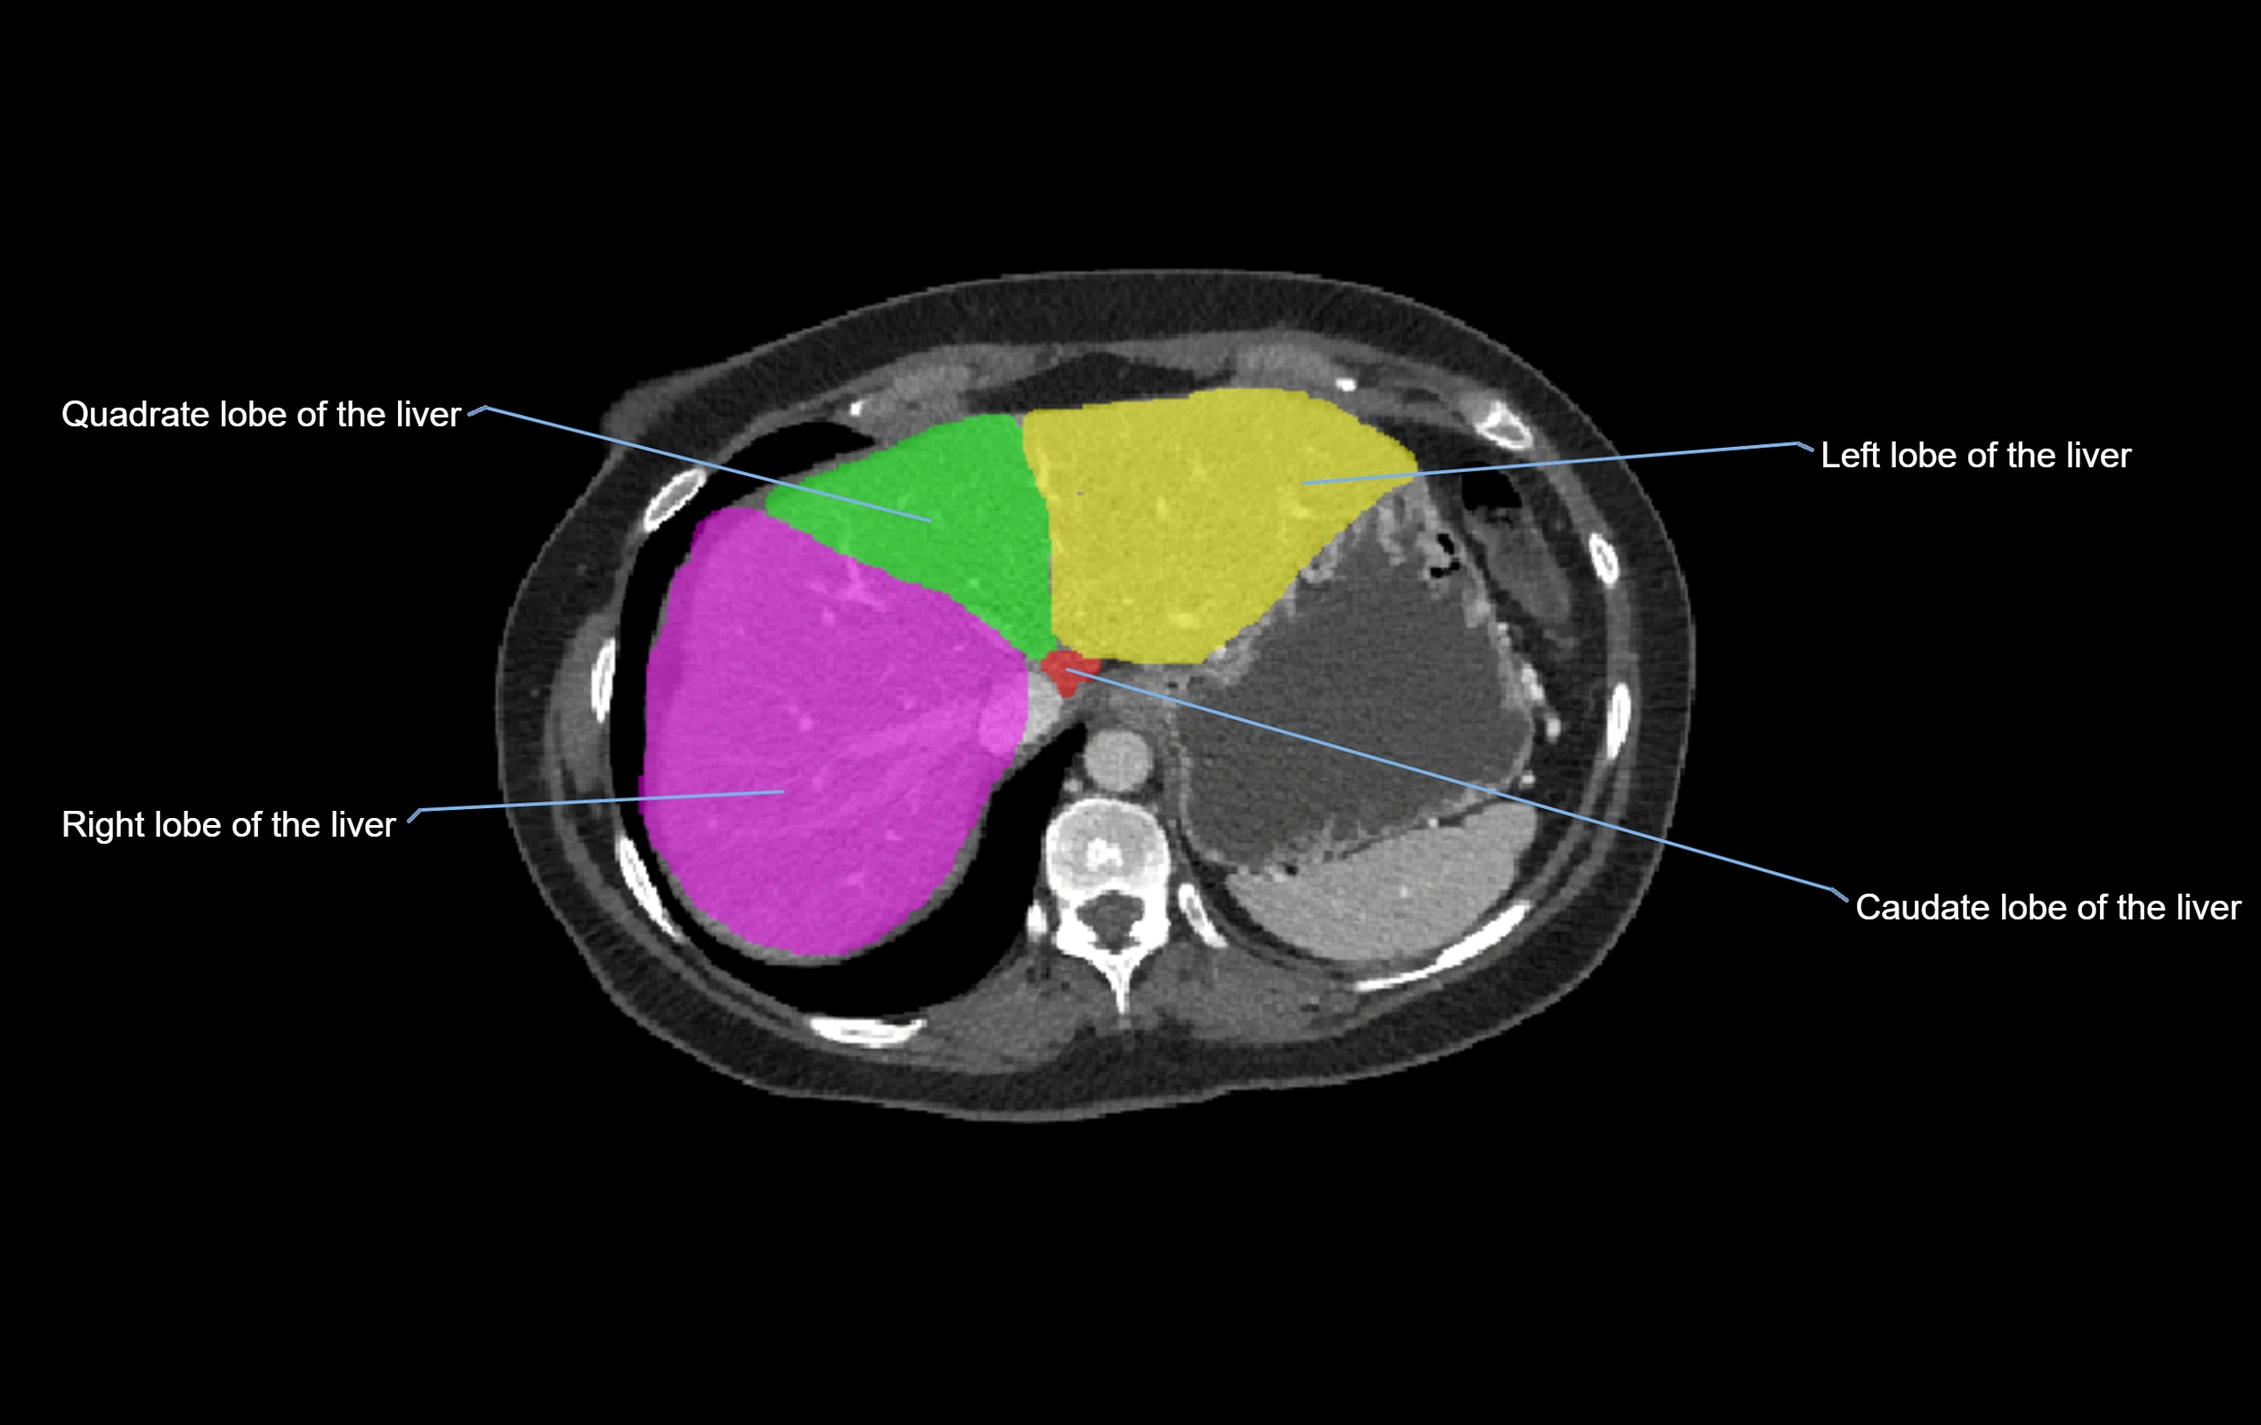

The caudate lobe of the liver is a distinct anatomical subdivision of the liver, designated as segment I in Couinaud’s classification. It lies on the posterior surface of the liver, between the fissure for the ligamentum venosum (left boundary) and the groove for the inferior vena cava (IVC) (right boundary). Superiorly, it is related to the posterior liver surface, and inferiorly it is separated from the left lobe by the porta hepatis.

The caudate lobe is unique because it receives dual portal venous and arterial inflow from both the right and left portal veins and hepatic arteries. It also has independent venous drainage directly into the IVC via multiple small hepatic veins, unlike other lobes that drain through the three main hepatic veins.

This anatomical autonomy makes the caudate lobe especially significant in liver surgery, transplantation, and hepatic venous outflow obstruction syndromes (e.g., Budd–Chiari syndrome). Enlargement of the caudate lobe is a characteristic imaging feature in chronic liver disease and cirrhosis.

• Segment I (Couinaud classification)

CT Appearance

CT Pre-Contrast:

• Caudate lobe appears as a soft-tissue density, isodense to the rest of the liver

• Enlargement may be appreciated in cirrhosis or Budd–Chiari syndrome

CT Post-Contrast:

• Homogeneous enhancement in the portal venous phase, similar to rest of liver

• Independent venous drainage into the IVC may be visualized

CT Venous Phase (functional significance):

• Caudate lobe often enhances relatively more than other lobes in Budd–Chiari syndrome, due to preserved venous outflow